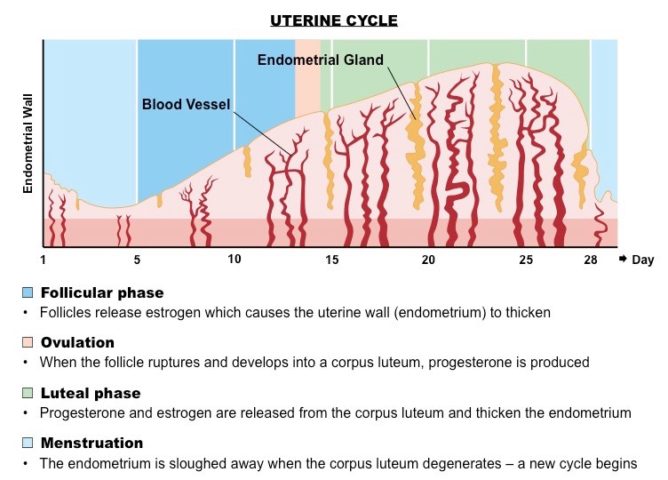

Solitamente la mestruazione inizia tra il 10° e il 17° anno di età (prevalentemente 12-14 anni) e solitamente dura circa 28 giorni.

Durante la prima fase del ciclo il follicolo inizia a svilupparsi, giungendo a maturazione attorno al 14°giorno) e rompendosi immediatamente dopo rilasciando un oocita secondario. Ciò che resta del follicolo si trasforma in corpo luteo che secerne progesterone. Tuttavia, se non si verifica la fecondazione, tale struttura va incontro a rapida regressione causando un significativo sfaldamento endometriale dovuto ad un repentino abbassamento dei livelli di progesterone e estrogeni.

Quando si parla di ciclo mestruale, possiamo macroscopicamente indentificare tre fasi distinte:

- Proliferativa = l’epitelio che circonda le parti basali delle ghiandole uterine inizia a crescere sull’endometrio, sfaldato dalla precedente mestruazione. Le cellule si moltiplicano in risposta a livelli crescenti di estrogeni, prodotti in maniera endogena direttamente dall’ovaio.

- Secretoria = coincide con la fase luteinica del ciclo ovarico. Durante questa fase l’endometrio è finemente regolato dal progesterone e dagli estrogeni secreti dal corpo luteo (attività secretoria dell’epitelio e delle ghiandole, espressione temporanea di nuovi geni, ispessimento endometriale, reazione deciduale, ecc…).

- Mestruale = al momento della regressione del corpo luteo si verifica una degenerazione contemporanea dell’epitelio ghiandolare e dello stroma. Ciò causa la rottura di numerosi vasi superficiali. Sangue e tessuto endometriale necrotico si accumulano inizialmente nell’utero per poi essere espulsi tramite la vagina in 3-6 giorni.